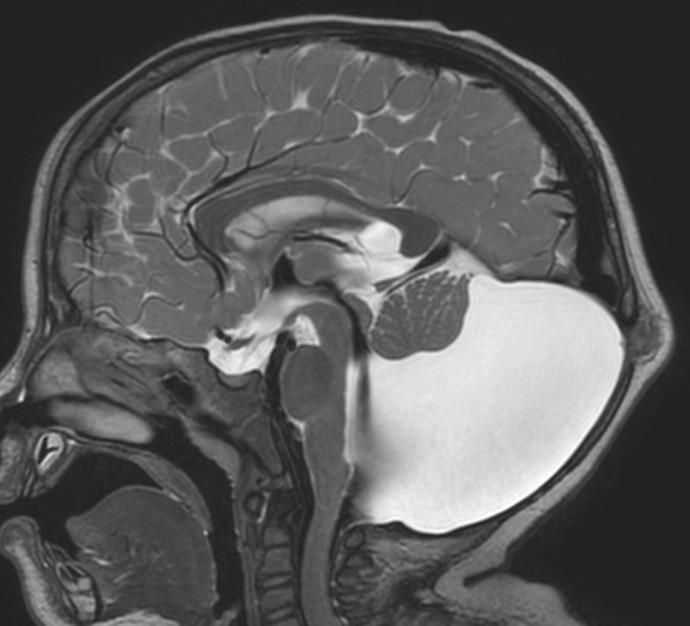

Sag T2 Cube nongated Normal

Normal

Sag T2 Cube

Nongated: CSF dephasing in the aqueduct on this sequence

Primary fissure 3 lobes Closed fastigial point

Sag T2 Cube Normal